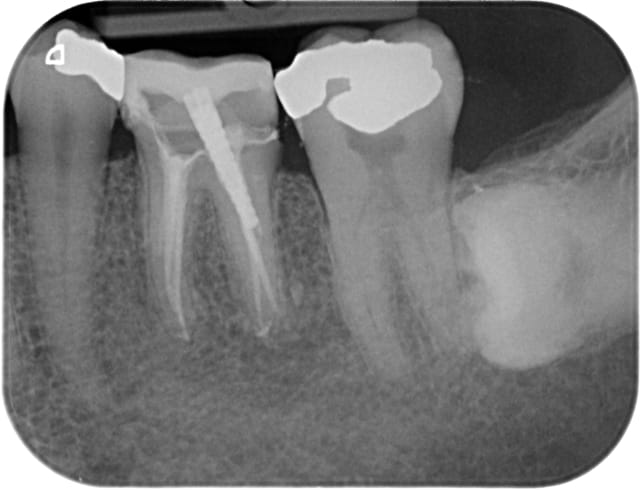

Moi capteur rvg, ca me suffit largement. La manipulation des plaques est éliminatoire pour moi.

Pas suffisamment fin pour détecter cette fêlure sur cette 26 qui sera à extraire ( infection, pas de vitalité) mais une radio argentique n'aurait pas fait mieux. -)